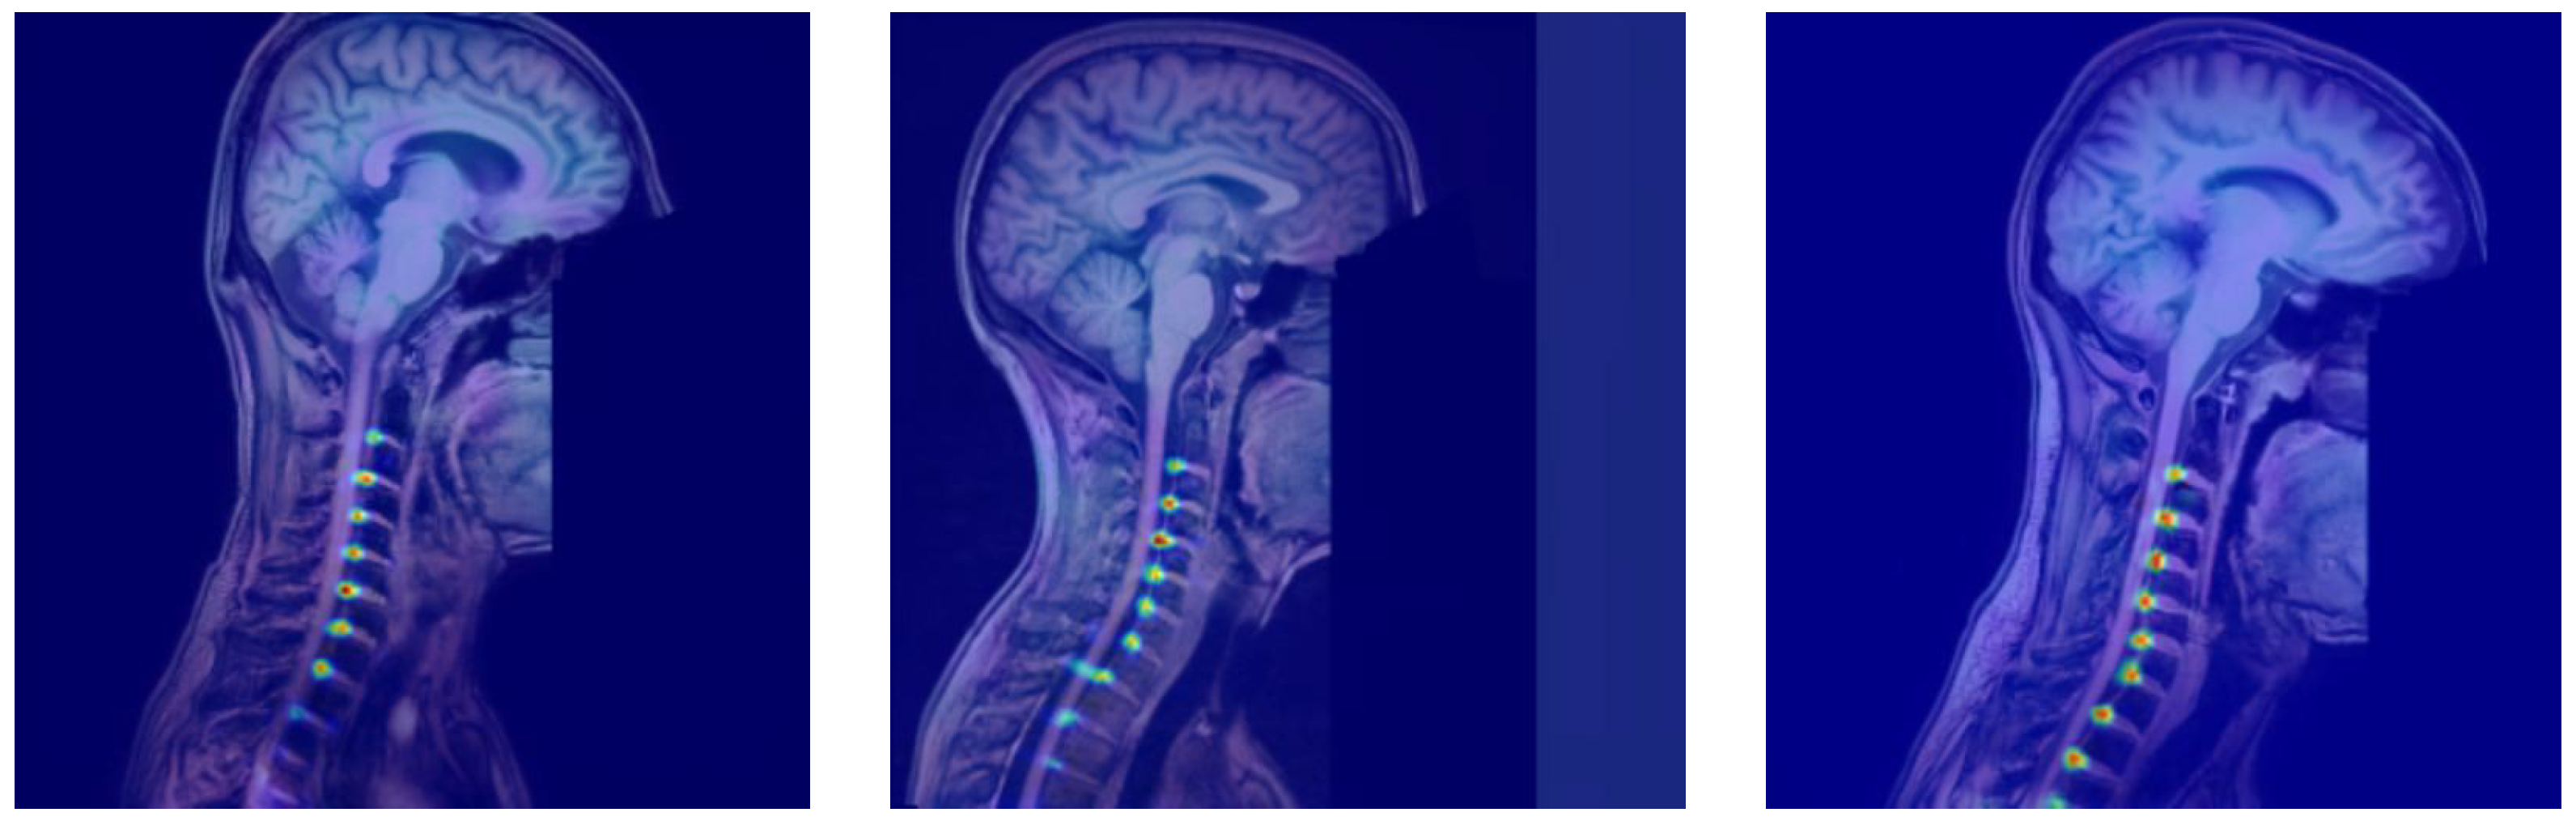

Distributional Stability Analysis on T2-Weighted MRI